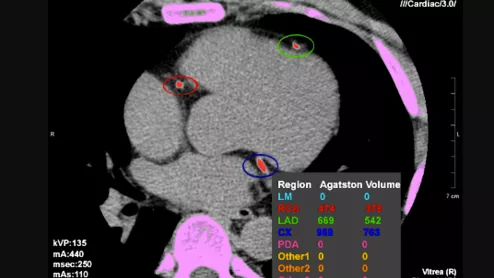

CT coronary artery calcium (CAC) scoring, also known as the Agatston score, to assess the risk a patient has for future heart attacks and help decide if a patient requires statins.